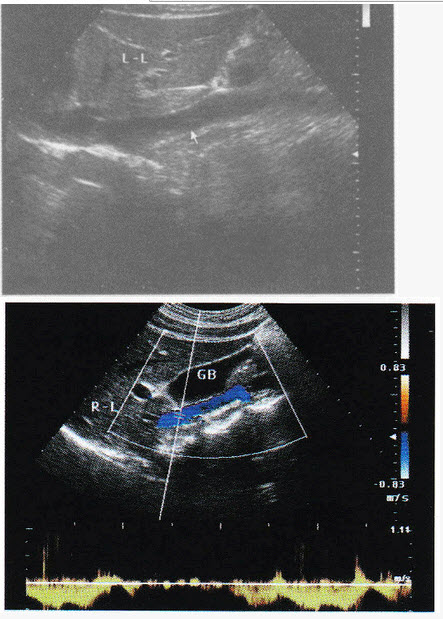

1、祝好点击这里查看我的门诊时间 北大医院张骞大夫郑重提醒因不能面诊患者,无法全面了解病情,以上建议仅供参考,具体诊疗请一定到医院在医生指导下进行参考资料北大医院张骞彩超中GB;办理病退的条件一是,丧失劳动能力,到指定医院鉴定二是,年龄男性满50周岁,女性可能是45周岁由本人提出申请关于退休待遇,养老金缴费必须满15年,可享受养老金待遇,拿多少养老金,按缴费年限和多少而定,不存在按80%或60%算这一说三是,关于医疗保险待遇,男性必须缴满30年,女性必须缴满。

2、1我厂在技术设计中,优化设计,精益求精,与设计院贵公司密切合作,保证设计工作的顺利开展,并积极听取4我方所供设备产品,其性能符合中国制定的G *** 282097柴油发电机组标准及ISO8528国际标准1 彩超室患者检查结束即时出具报告,CT及普放患者急诊半小时出具报告,平诊两小时出具报告,疑难病例两日彩超中GB;结合全新的技术平台,保证更佳图像性能的完美呈现高性能豪华型全数字主机高亮度高分辨率彩色医用液晶显示器高灵敏度超大触摸屏,让医生在临床应用中享受更多的操作乐趣最新计算机平台设计采用最新的Windows操作系统,功能更丰富,性能更稳定 采用PIV30GHz的双系统CPU,560Gb的系统硬盘,知您所需;对,多躺着别乱活动, *** 口开了害怕彩超中GB你流产 cn#GVfpLBQGB 20140610 1906 我是学医的,流出来的是少量的羊水,宫口以开,前三个月是最危险的,好好保胎,要卧床休息,避免劳累,负重,房事,剧烈咳嗽 百度知道用户 20140610 1907 听医生的 cn#BQuGGpQauu 20140610 1910 加载更多相关;建议检查尿红细胞形态,还可以送检尿培养,看有无泌尿道感染,另外建议检查肺炎支原体抗“O”补体等待明确诊断后可进一步治疗厦门市妇幼保健院儿科 *** 主任医师 查看原帖。